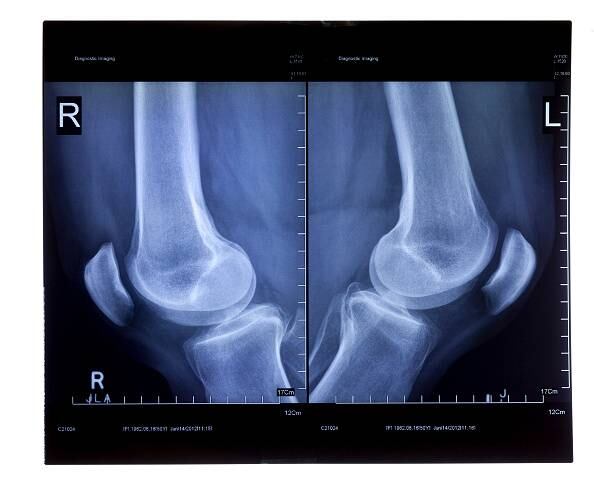

Acorde a una investigación de la Escuela Imperial de Londres, se trata de la fabela, el cual es un pequeño hueso que se encuentra incrustado en un tendón detrás de la rodilla.

Sin embargo, para el 2018 el hueso se encontraba en el 39% de la población mundial, algo que los científicos no logran comprender, tomando en cuenta además que los expertos tampoco logran dilucidar cuál es la función de la fabela.